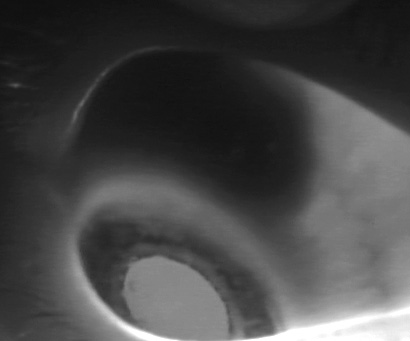

Transillumination the globe allows you to see the extent and borders of an anterior located tumor.

Often a surgical procedure can be planned after visualizing the extent of the tumor borders. A big concern is if the tumor is in the cilliary body and would include the iris.